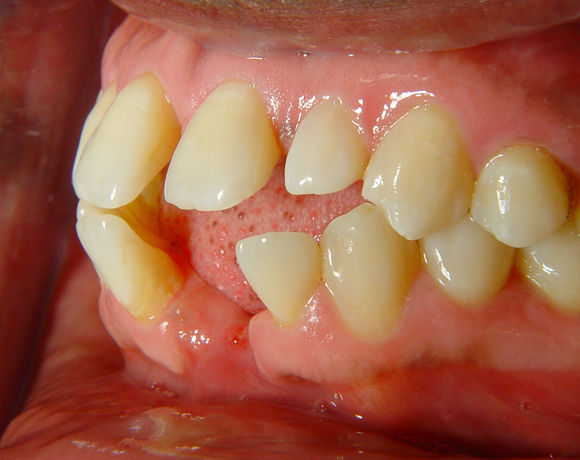

Diese Frontzahnsituation stellte den Behandler vor größere Probleme

Durch Abrasion der Seitenzähne wurden die Frontzähne nach labial verdrängt und lückig. Nach Verlust des Zahnes 41 entstand eine Lücke in der drei Zähne Platz fanden. Auch im Oberkiefer wurden die lateralen Lücken mit Veneers verkleinert.